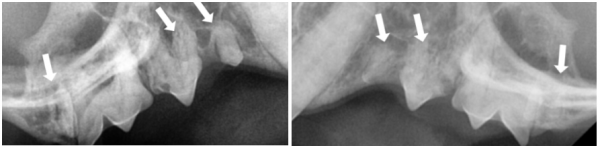

dda74ec2cbe3c1a8b77df26586ebe9fb_1765777786_9241.png

→ 우측·좌측 상악 어금니

106,107,109 치아흡수성병변

206,207,209 치아흡수성병변

치과 방사선 촬영에서

육안으로 확인되었던 치아 이외에도

다수의 치아흡수병변이 있는 것으로 확인되었습니다.

고양이 치아흡수성병변

육안으로 확인이 어려운 경우가 많아

치과 방사선 촬영이 필수적입니다.

치아 내부의 흡수 정도와 남아 있는 치근 상태를 정밀하게 평가해야 합니다.